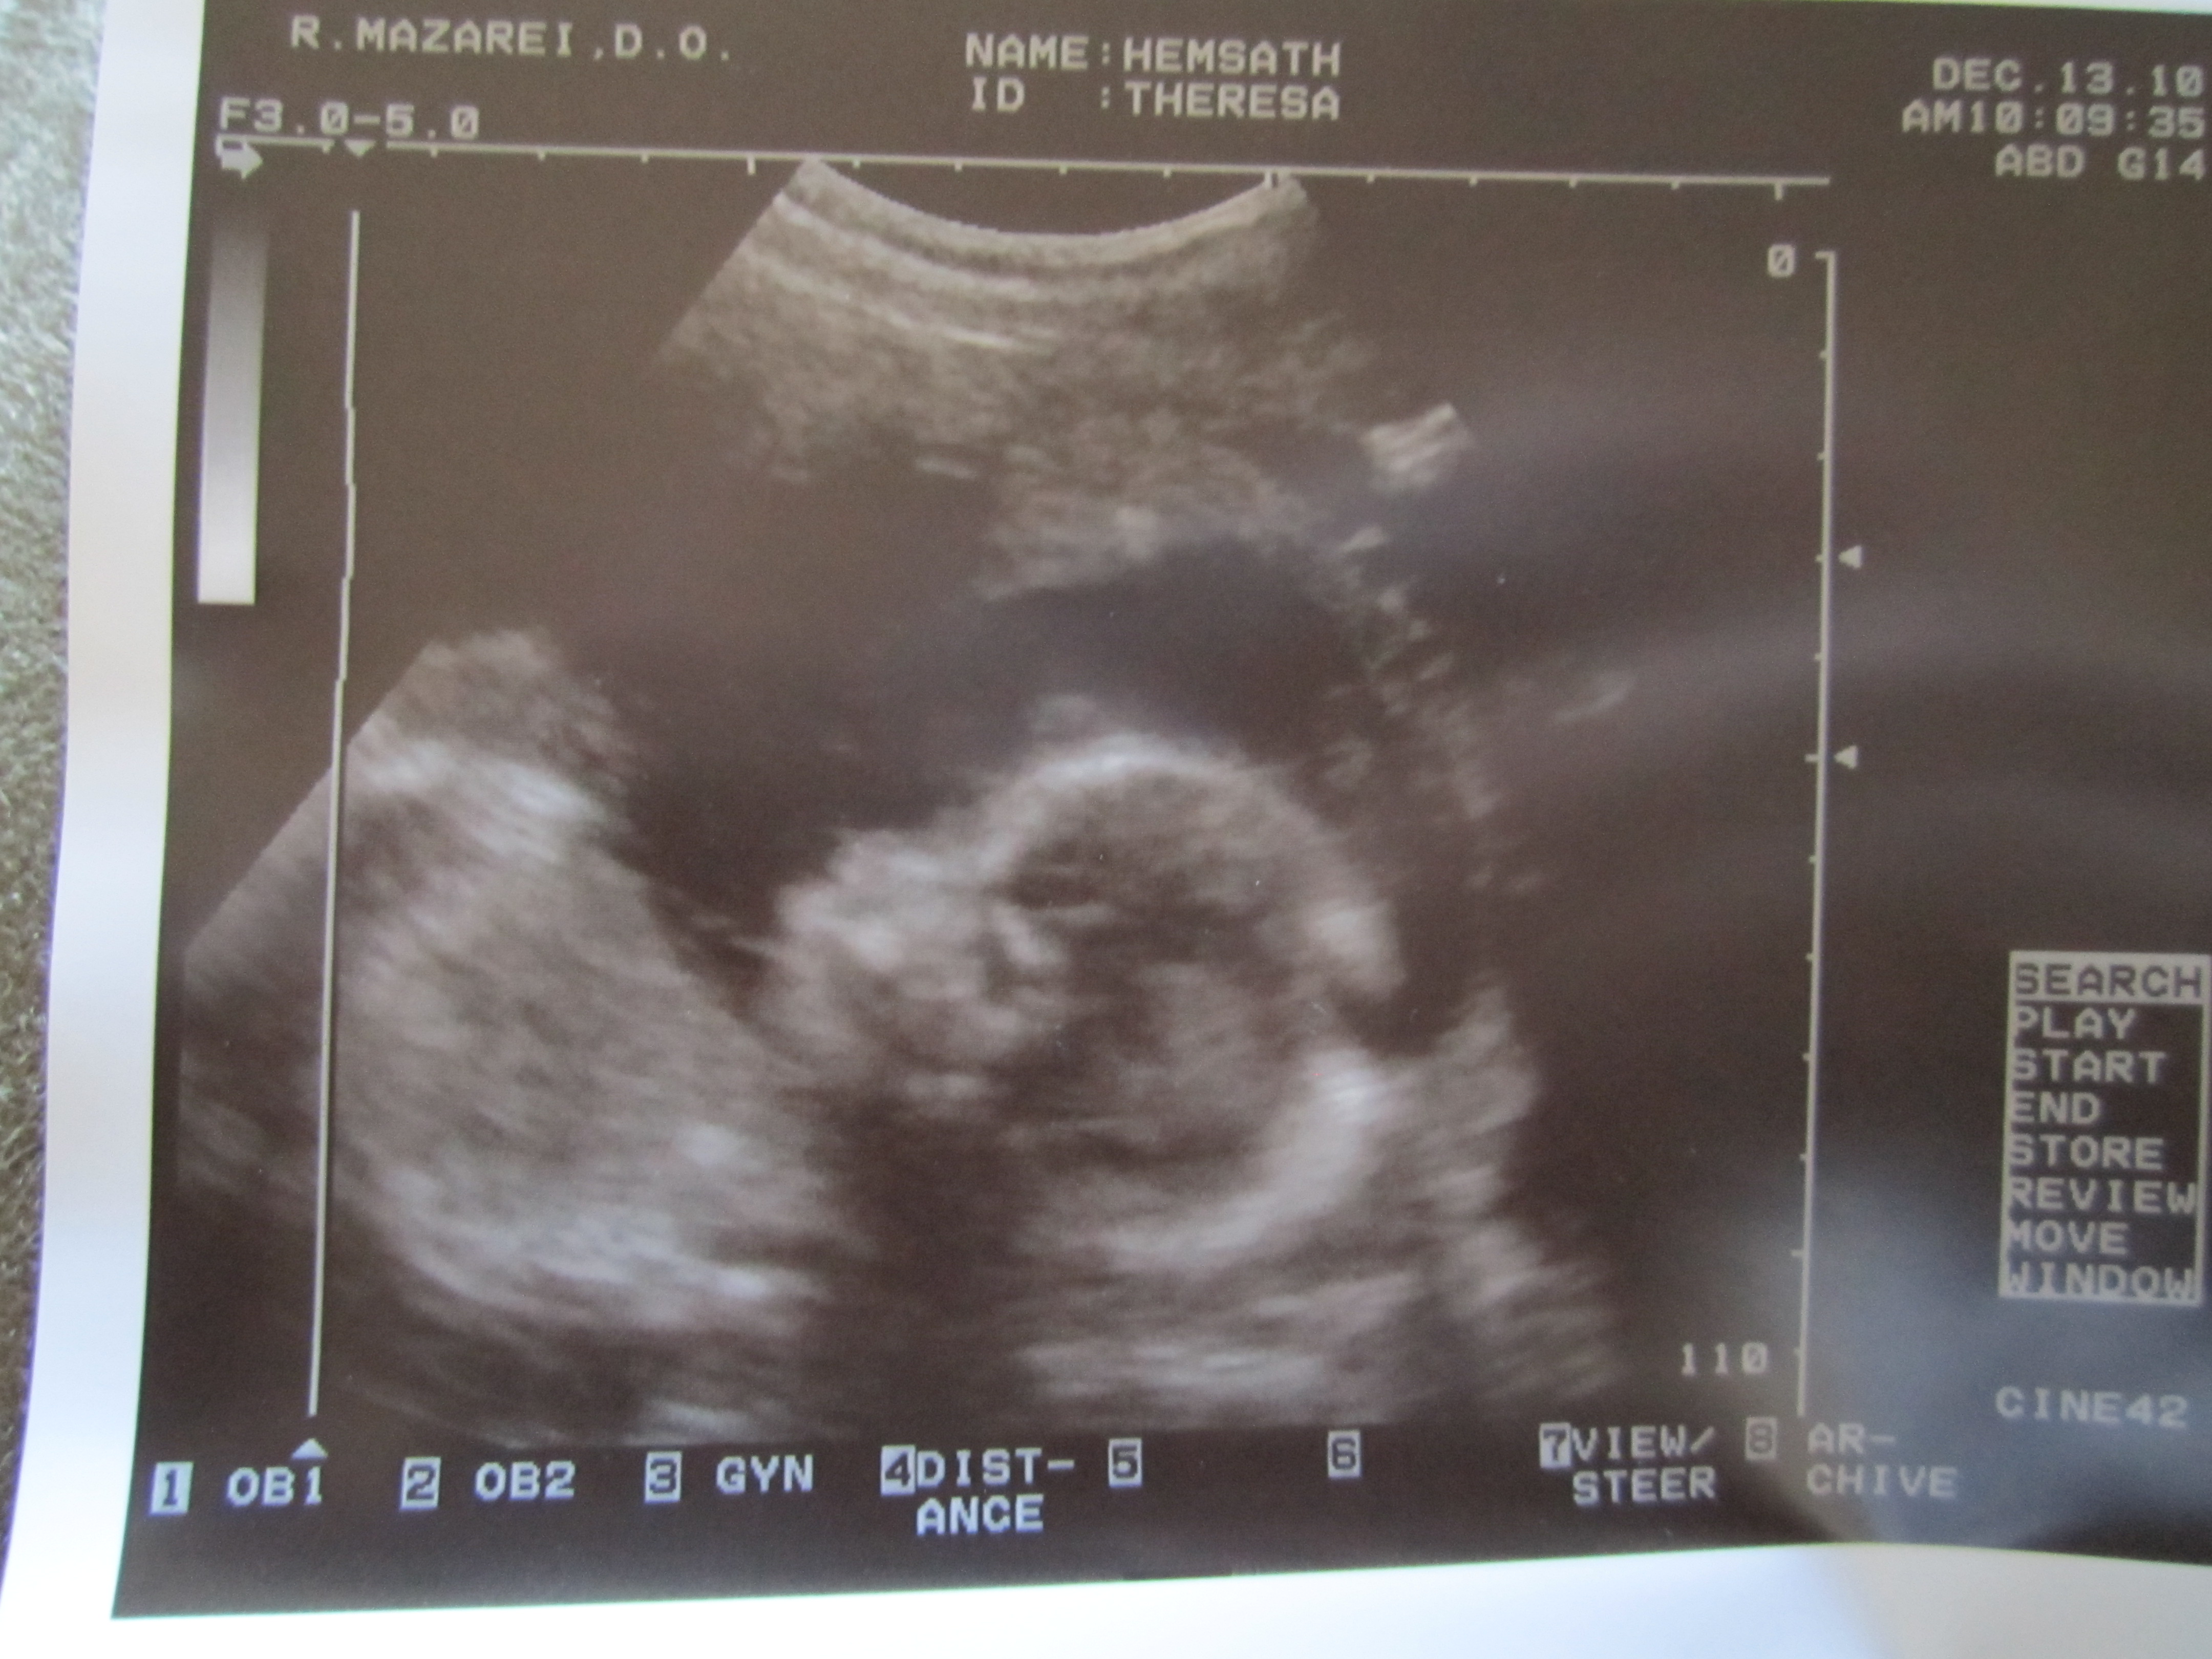

- Talking to Kanan about the baby. He kisses my belly. He tells me he loves his baby brother or sister. He wants him to be a girl and to name her Allison (Even though the ultrasound showed us it is a boy and we think we may name him Mathias or Mateo). He wants me to hold the baby and him or to have Papa (Owen’s name) hold the baby and I hold him. He wants to help feed the baby and hold the baby too. So darn cute! Oh yeah, and he loves watching videos from Baby Center that shows the development of the baby in the womb.

- All the medical scares that come with being pregnant in the 21st century. What ever happened to just being pregnant and having a baby? Now I’ve got to do blood tests and ultrasounds and if anything is slightly off, they scare me with all the what if’s, risks, and possibilities and then want me to do all these other medical procedures. I believe it’s a greedy conspiracy for money.